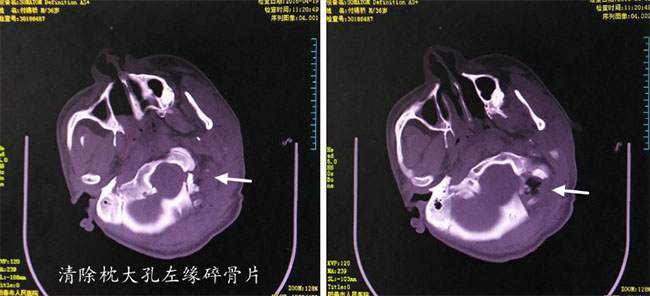

术后CT提示枕大孔左缘碎骨片清除,术中成功止血

患者付某为37岁男性,因“高处坠落伤及头部,昏迷10余小时”于4月18日23时30分由外院转入。入院时呈中度昏迷状态,GCS评分6分。双侧瞳孔不等大,右侧直径3.0毫米,左侧5.0毫米,对光反射消失。头部CT提示:1. 左侧颞顶枕部大量硬膜外血肿;2. 左侧小脑硬膜外血肿;3. 枕骨骨折。由于枕骨大孔左缘粉碎性骨折伤及颅颈交界区左侧颅底重要结构(枕髁、椎动脉、乙状窦、颅底静脉丛和硬脑膜),手术会引起大量出血且不易止血,风险极高。迅速完善术前准备并与家属详细沟通后,我院神经外科为其施行“左侧颞顶枕部及左侧小脑硬膜外血肿清除术+枕大孔左缘探查碎骨片清除”,术中对枕大孔左缘颅底大量动静脉出血成功止血并清除局部碎骨片。